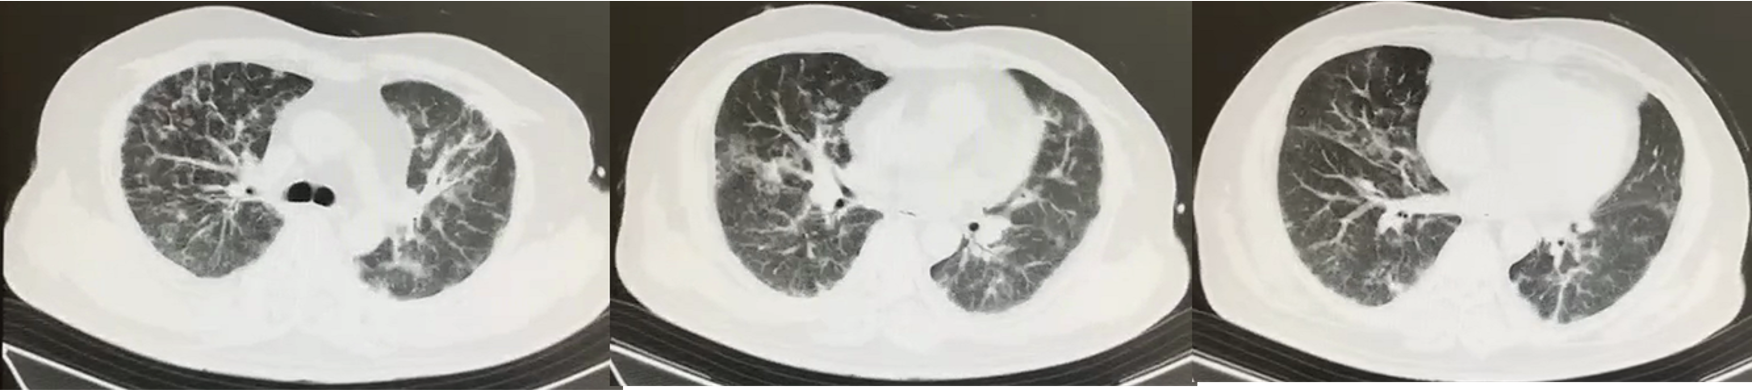

胸部CT(2021-8-15):双肺多发间质性炎症,以双上肺为著。

2021-8-13 双肺多发间质性炎症,双上肺为著

2021-9-2 双肺多发间质性肺炎较前明显加重

2021-9-6 双肺多发间质性肺炎较前变化不大

2021-9-16 双肺多发间质性肺炎较前稍减少